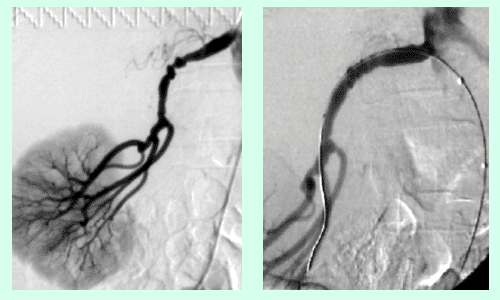

Abbildung 6a,b: Während und nach Stent-Implantation bei demselben Patienten.

Abbildung 7a,b: Patientin mit Bluthochdruck (160/110 mmHg unter Therapie) – beidseitige Nierenarterien-Stenose – vor und nach Stent.